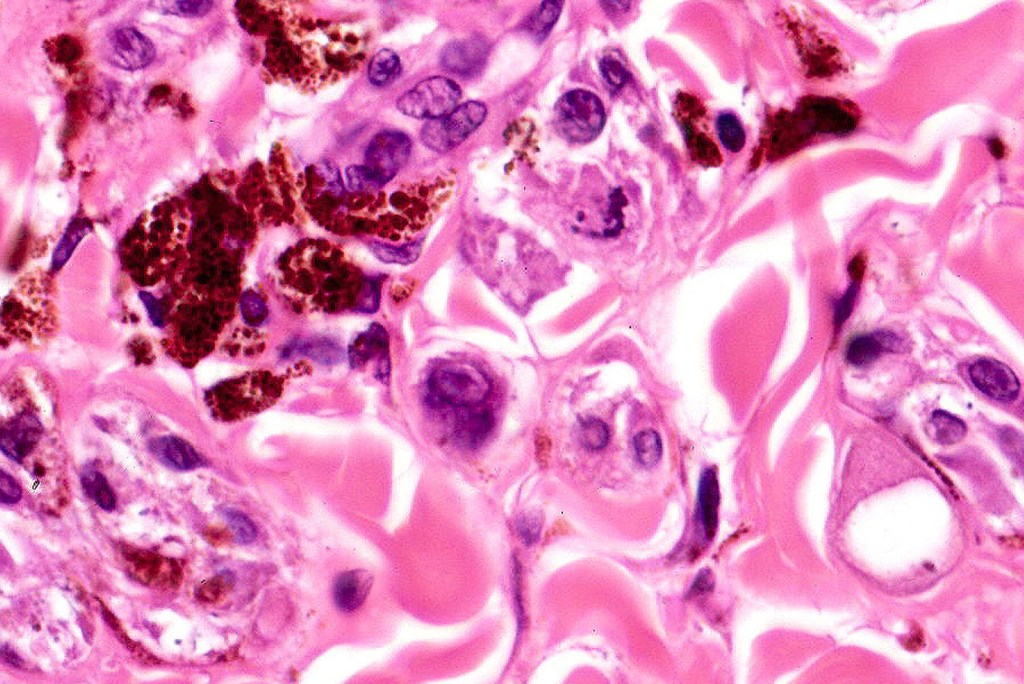

•Admixture of spindle cells, pigmented bipolar or dendritic cells & melanophages

•Cytoplasm is pale and nuclei are small with inconspicuous nucleoli

•An alveolar pattern is characteristic particularly with clear cell nodules

•Multinucleate giant cells sometimes present

•Stromal fibrosis, myxoid change, vascular hyalinization with cyst formation are often seen

•Balloon cell change